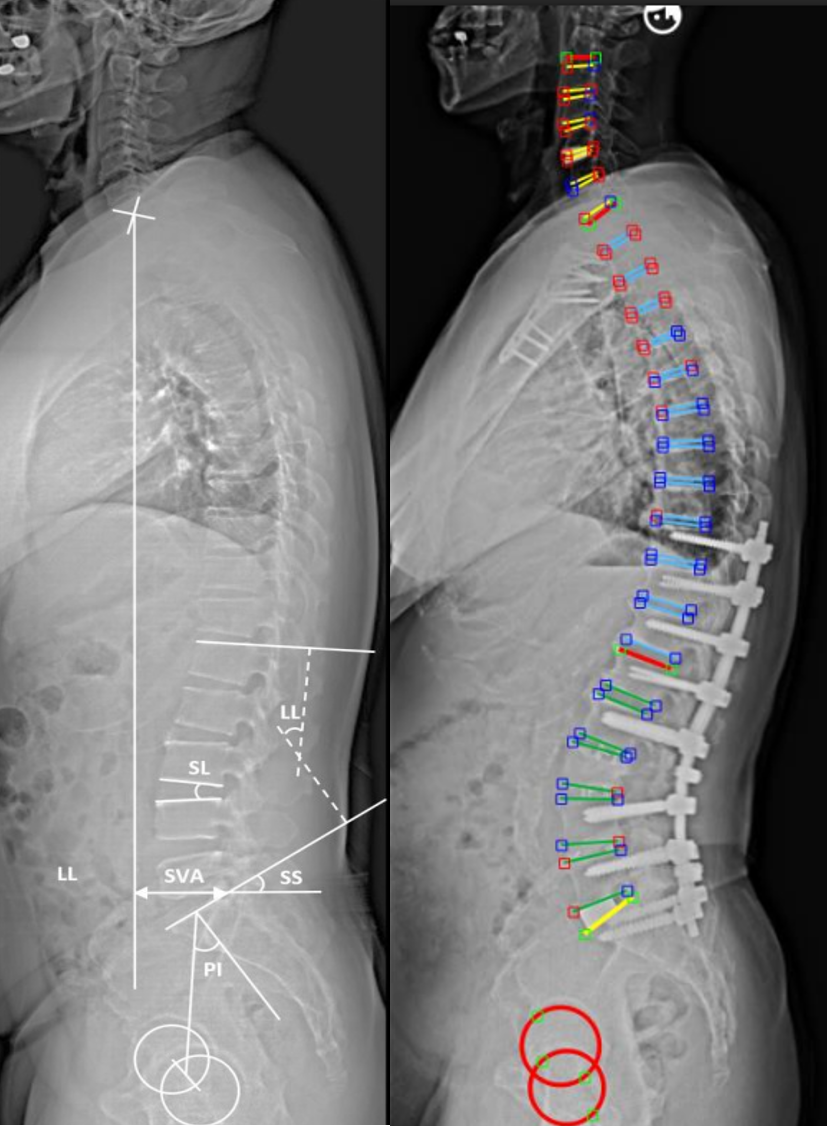

- Advanced Minimally Invasive Techniques: We utilize state-of-the-art minimally invasive and microscopic surgical methods, including AI-assisted navigation systems and robotic guidance, which enhance surgical precision and safety.

- Innovation in Robotic-Assisted Surgery: VGHTPE is preparing to introduce the latest robotic-assisted spine surgery system. This technology can achieve up to 99% accuracy in pedicle screw placement, improving surgical safety, and minimizing complications such as nerve injury and implant malposition . With intelligent planning software and real-time navigation, the robotic system streamlines surgical steps, shortens operation time, and minimizes X-ray exposure, benefiting both traditional and minimally invasive spinal deformity surgeries.

Traditional open spinal deformity correction remains the standard for treating severe, complex, or multi-level spinal deformities. This approach involves a longer incision to provide direct access to the affected spinal segment, allowing for comprehensive correction, implant removal or replacement, bone fusion, and nerve decompression if required. Traditional surgery is especially beneficial for advanced degenerative spinal deformity, severe rotational deformities, or cases failed previous surgeries. Traditional open procedures at VGHTPE may be further enhanced with the addition of robotic-assisted technology to maximize accuracy and patient safety.

For selected patients, minimally invasive spinal deformity surgery offers several advantages, including smaller incisions, less tissue disruption, reduced blood loss, and faster recovery times. Utilizing advanced tools such as tubular retractors, endoscopic or microscopic visualization, AI-assisted navigation, and robotic guidance, our surgeons can achieve effective spinal correction with less trauma to surrounding tissues. With the anticipated introduction of the robotic-assisted system, minimally invasive surgeries will achieve even greater precision and efficiency. Many patients are able to start walking as soon as the second day after surgery and typically experience shorter hospital stays and less postoperative pain.